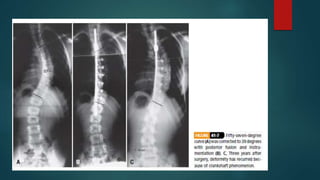

 CRANKSHAFT PHENOMENON:

 With a solid posterior fusion, continued

anterior growth of the vertebral bodies

causes the vertebral body and discs to

bulge laterally toward the convexity and to

pivot on the posterior fusion, causing loss

of correction, increase in vertebral rotation,

and recurrence of the rib hump.

3)Crankshaft phenomenon